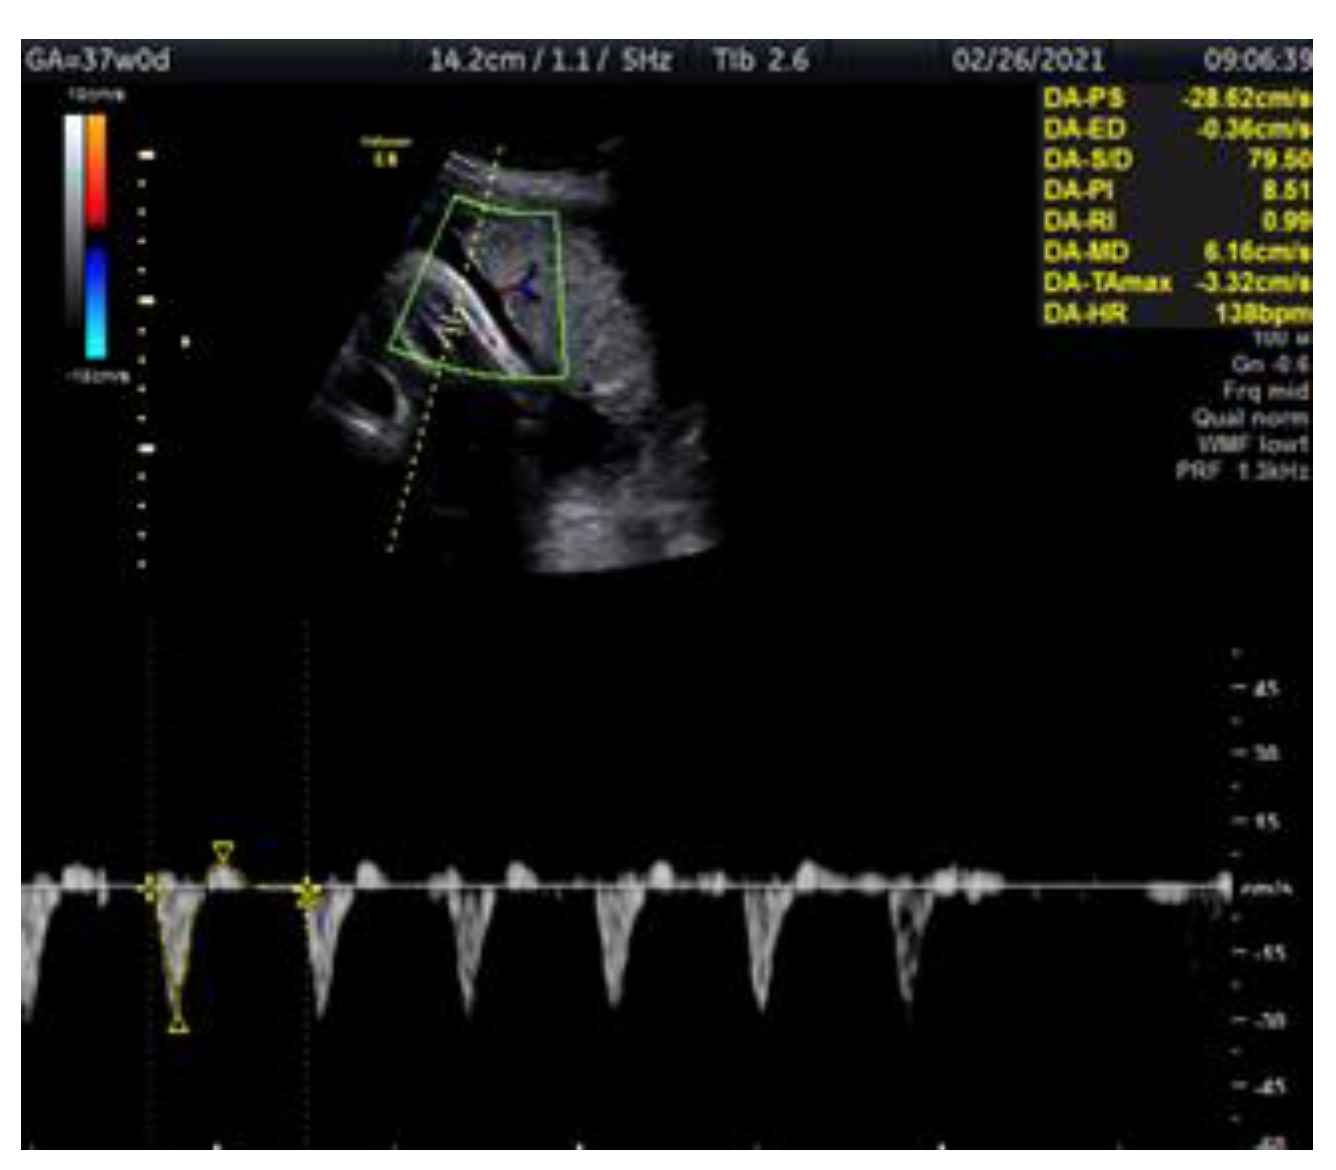

Doppler Ultrasonography of the Fetal Tibial Artery in High-Risk Pregnancy and Its Value in Predicting and Monitoring Fetal Hypoxia in IUGR Fetuses

2. Case Report